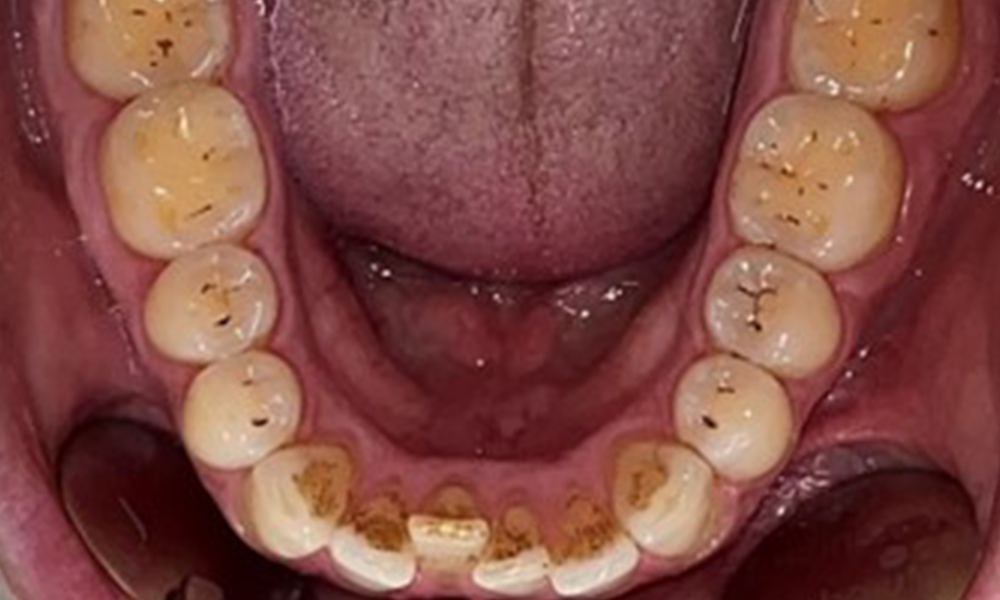

Le patient a une dentition complète avec un total de 28 dents. Il y avait des érosions et des attritions notables. (Fig. 4, Fig. 5). En raison du bruxisme, le patient a porté pendant de nombreuses années une attelle avec une gouttière ajustée la nuit. Les érosions ont été causées par une consommation prolongée de boissons isotoniques. Aucune perte d'os parodontal ou carie active n'a été observée.

Une denture adulte complète, sans carie ni perte osseuse radiologiquement reconnaissable, a été observée (Fig. 6). La perte radiologique d'émail et de cuspides était particulièrement évidente sur les 36 et 37.